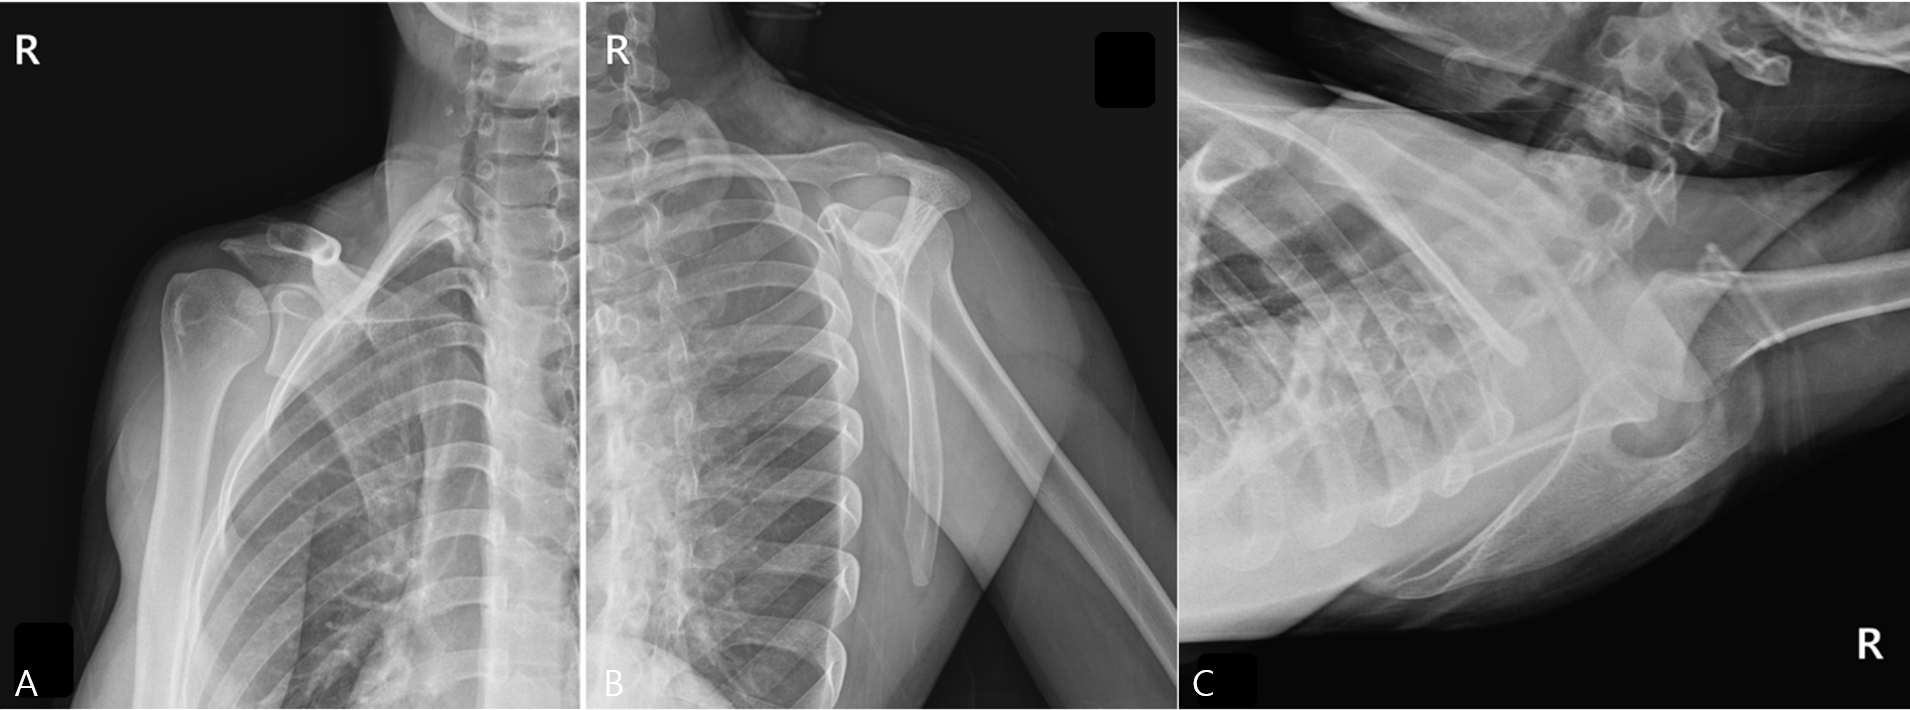

Figure 1. Plain Radiographs of the Right Scapula. These radiographs were taken due to the worsening of wrist symptoms, accompanied by a feeling of instability in the scapular region. (A) True anteroposterior (AP) view of the shoulder, (B) scapular Y-view, and (C) axillary view. All views showed no evidence of a definite fracture line, dislocation, or other specific abnormalities.

Radiographs, including true anteroposterior, Y, and axillary views, showed no abnormality [Figure 1], but the MSK ultrasound revealed cortical irregularity in the right scapular body, corresponding to the site of pain. Two distinct longitudinal views were obtained: one directly over the medial scapular border showing a subtle cortical irregularity, and another medial to the border revealing a more extensive cortical disruption with a longer fracture line [Figure 2]. Sonoguided digital palpation was performed, and localized tenderness was observed at the site of cortical irregularity, leading to a provisional diagnosis of scapular fracture. The chronological sequence of clinical events, diagnostic imaging, and interventions is summarized in Table 1. Following the suspicion of a scapular fracture, treatment focused on both potential fracture healing and the restoration of scapular stability [21]. Prolotherapy injections were administered to the right scapular medial border and surrounding ligaments to promote structural stability. Prolotherapy was administered using a solution of 10% dextrose. Under ultrasound guidance, approximately 5 mL of the solution was injected into the periosteum and surrounding tendons at the site of cortical irregularity on the medial scapular border. This procedure was repeated bi-weekly for a total of 4 sessions over two months.